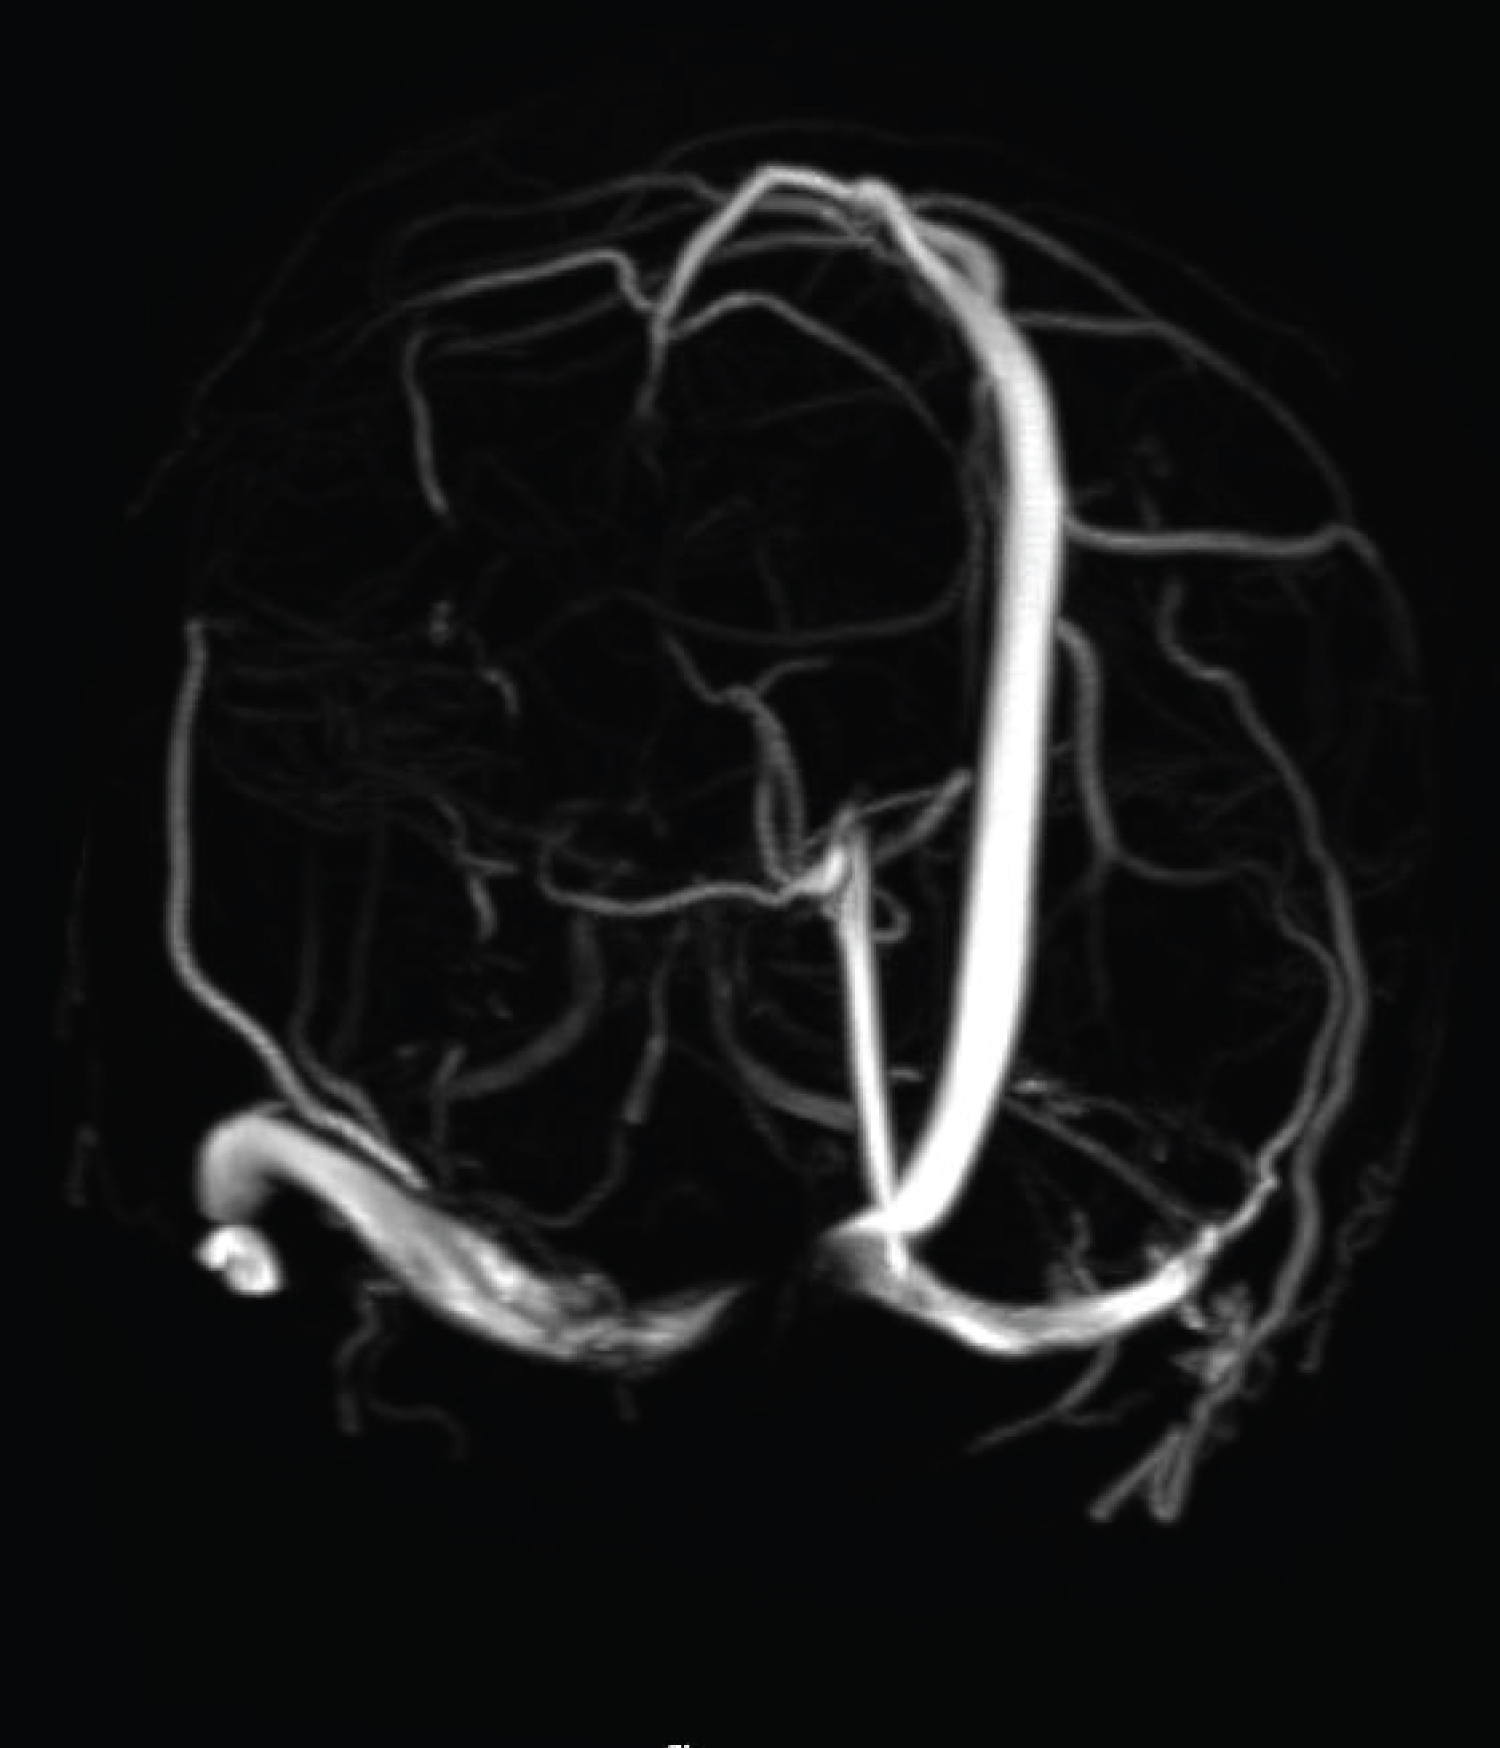

In our case, the patient was an adult, diagnosed with a palpable mass at his occiput, which was proven to be an intraosseous epidermoid cyst, compressing on the confluence of the sinuses, causing increased ICP and visual symptoms and papilloedema. It is advisable for scalp lesions, especially overlying important anatomical structures, to perform brain imaging, before attempting excision (Figure 1, Figure 2, Figure 3 and Figure 4).

Figure 3: 3D MR venogram time-of-flight shows interruption of the normal flow in the right proximal transverse sinus due to compression of underlying intraosseous epidermoid. Note normal straight sinus. View Figure 3